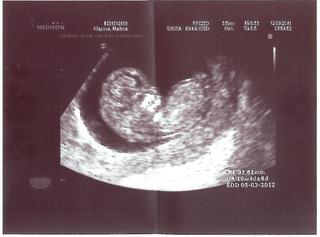

Ahoj holky, jen tak dál, to je paráda, že takhle krásně těhotníte 🙂 Držim palce na prvních kontrolách a ještě sem pak kouknu. U mě to letí, začínám 23. tt a podle UZ už dokonce 25. Už mi začíná tvrdnout břicho a malej tam sebou hází, že to asi nebude klidné miminko 🙂

@denousek Tak s timhle ti moc nepomuzu. Ja to vubec nesledovala 🙂 Ani ovulaci na sobe asi nepoznam a zkratku DPO jsem videla poprve tady 😀 Posledni MS jsem mela 24.5. Na ultrazvuku jsem byla az 20.7. Doktor rikal, ze podle UZ je to 7plus2, podle MS by to melo byt byvalo o par dni vic. Ja hlavne mela prvni cyklus po dobrani antikonepce, takze asi dost rozhazeno..